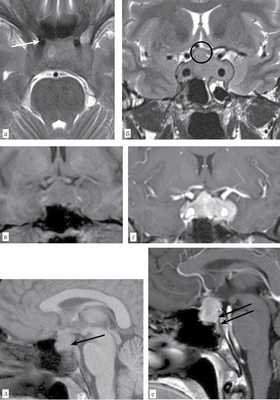

При ретроспективном анализе МРТ головного мозга пациента № 1 с контрастным усилением выявлено увеличение поперечного и вертикального размера гипофиза, утолщение воронки, потеря дифференцировки между адено- и нейрогипофизом и отсутствие характерного гиперинтенсивного сигнала Т1-взвешенного изображения (ВИ) от нейрогипофиза. Верхний полюс увеличенного гипофиза компримировал хиазмальную цистерну и хиазму. Измененный гипофиз имел среднеинтенсивный сигнал на Т2-ВИ и Т1-ВИ. В правой половине выявлялась локальная зона отека. После введения контраста отмечалось интенсивное гомогенное усиление от всего гипофиза и накопление утолщенными менингеальными оболочками контраста в виде «усиков» по скату основной кости (рис. 4).

Рис. 4. Больной № 1. Т2-ВИ гипофиза в аксиальной (а) и фронтальной (б) плоскости. Железа увеличена в размерах в параселлярном и супраселлярном направлениях, Утолщена воронка (обозначена кружком). На фоне среднеинтенсивного сигнала выявляется локальная зона отека (обозначена стрелкой). Сифоны внутренней сонной артерии интактны. Т1-ВИ гипофиза во фронтальной плоскости до (в) и после (г) внутривенного контрастного усиления. Сигнал от пораженной железы достаточно гомогенный, среднеинтенсивный. Отмечается интенсивное гомогенное контрастирование ткани гипофиза. Сифоны внутренней сонной артерии интактны. Т1-ВИ в сагиттальной плоскости до (д) и после (е) внутривенного контрастирования. До контрастирования визуализируются выраженный супраселлярный тип роста железы, отсутствие типичного высокоинтенсивного сигнала от нейрогипофиза (указано стрелкой). На постконтрастном изображении отмечается равномерное контрастное усиление железой и наличие контрастного усиления по утолщенной менингеальной оболочке вдоль ската основной кости (указаны желтыми стрелками), а также контрастированные менингеальные «усики» (указаны красными стрелками) или феномен «dural tail».

Все МРТ-исследования головного мозга проводились вне ФГБУ «СЗФМИЦ им В.А. Алмазова». При ретроспективном пересмотре МРТ-снимков у больного № 1 выявлены признаки гипофизита: 1) симметричное увеличение с супраселлярной экспансией; 2) утолщение воронки без смещения; 3) гомогенное интенсивное контрастирование; 4) появление «дурального хвоста» на сагиттальном срезе; 5) снижение яркости «пятна» гипофиза, т. е. правильный диагноз мог быть поставлен.